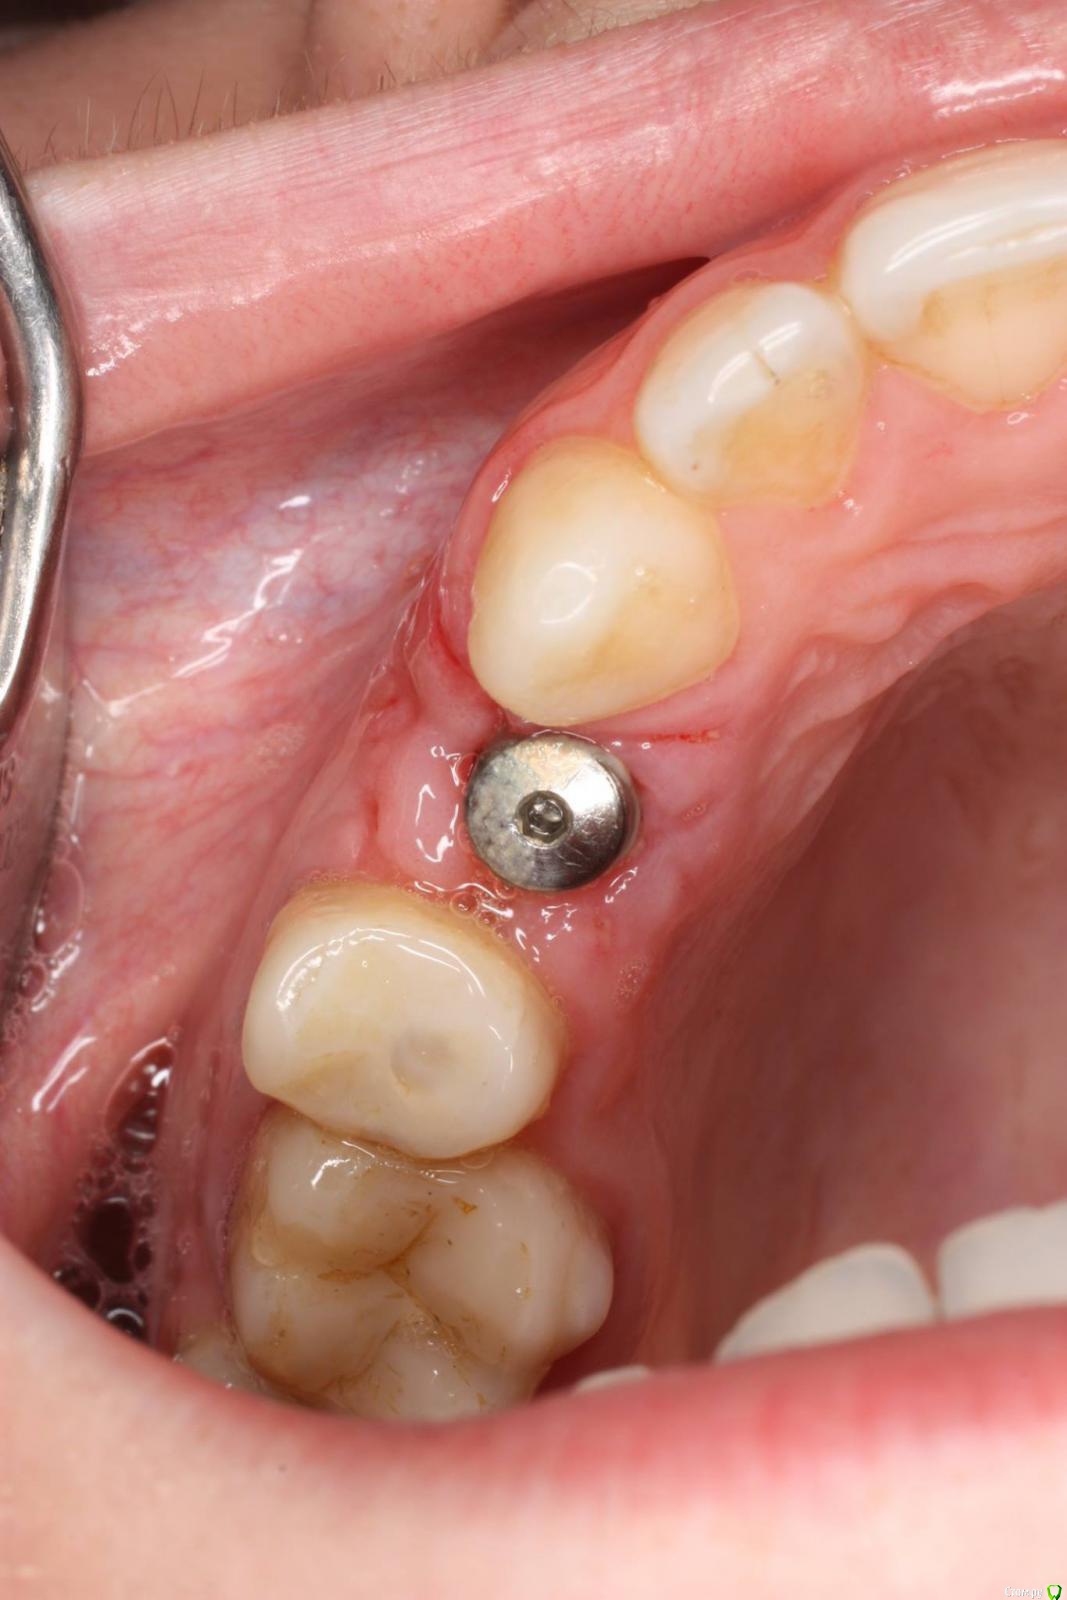

togrul Опубликовано 24 ноября, 2016 Поделиться Опубликовано 24 ноября, 2016 Имплантация проводилась 6 месяцев назад . Пациентка запротезирована. Это моя 2 имплантация была . 7 Ссылка на комментарий

togrul Опубликовано 24 ноября, 2016 Автор Поделиться Опубликовано 24 ноября, 2016 Нет Bio oss использовали . Ссылка на комментарий